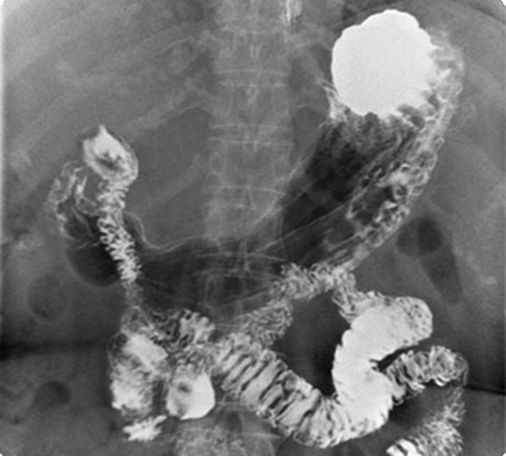

Upper GI series的基本投照方式有:

- 右前斜位(RAO)

- 後前位(PA)

- 右側位(right lateral)

- 左後斜位(LPO)

- 前後位(AP)

Erect

胃底充滿空氣

可見明顯的氣液面